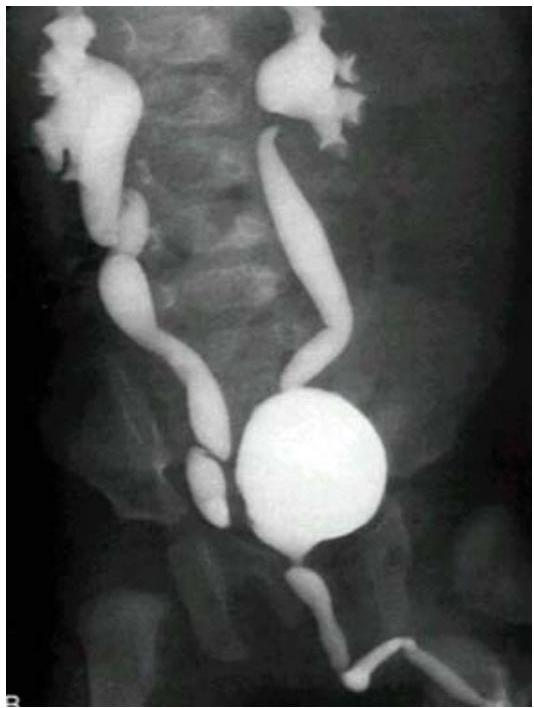

Vesicoureteral Reflux (VUR) — MCUG/VCUG

Scenario: Infant referred for evaluation following recurrent UTI.

Investigation? Micturating cystourethrogram (MCUG) / Voiding cystourethrogram (VCUG)

Findings?

- Posterior urethral valve

- Dilated ureters and bladder

- Tortuous ureters

- Dilated renal pelvis and calyces bilaterally (hydronephrosis)

Diagnosis? Vesicoureteral Reflux (VUR) — grade 4-5.

Diagnosis & Grading

- Studies: Renal US (Typically first); MCUG (to confirm diagnosis); RNC (for follow-up).

International Grading System (MCUG Findings):

| Grade | Description / Findings |

|---|---|

| Grade I | Into a nondilated ureter only. |

| Grade II | Into the pelvis and calyces without dilation. |

| Grade III | Mild to moderate dilation of ureter, pelvis, and calyces; minimal blunting of fornices (become close). |

| Grade IV | Moderate ureteral tortuosity and dilation of pelvis and calyces (adhered to each other). |

| Grade V | Gross dilation; significant tortuosity; loss of papillary impressions; blunting of calyces (bilateral/severe). |